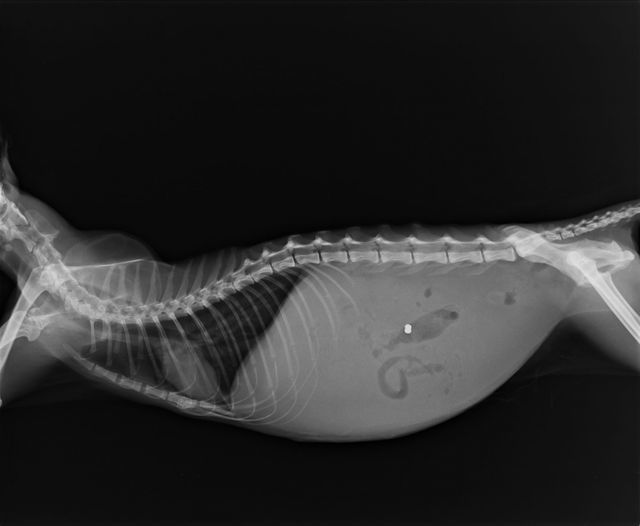

Что такое асцит

Асцит у кошек — это несамостоятельное заболевание, связанное с накоплением жидкости в брюшной полости. Асцит поражает внутренние органы и может привести к гибели питомца. Второе название болезни — брюшная водянка. Если у вашей кошки «надулся» живот, она стала вялой и слабой, возможно, что у неё именно асцит.

Асцит — это водянка, скопление жидкости в животе кошки

Асцит является одним из признаков какого-либо заболевания, поэтому водянку часто путают с другими болезнями.

Наиболее типичный признак синдрома — увеличение живота в объеме. Симптомы раскрываются постепенно, в зависимости от скорости накопления вещества. При чрезмерном количестве транссудата брюшина становится большой и тугой.

Домашним тестом для определения асцита служит одна простая манипуляция. Кота следует поставить на задние лапы. Если живот стал похожим на грушу, с характерным для этого фрукта расширением в нижней части, нужно немедленно показать питомца ветеринару.

Главным проявлением асцита считается грушевидная форма живота животного в стоячем положении

По возвращении животного в исходное положение через несколько минут брюшко приобретает прежние очертания. Подобный эффект происходит в результате стекания жидкости вниз. У кошек с длинным подшерстком присущее асциту увеличение брюшины будет малозаметно. Симптоматика обусловлена степенью тяжести недуга и скоростью накопления транссудата.